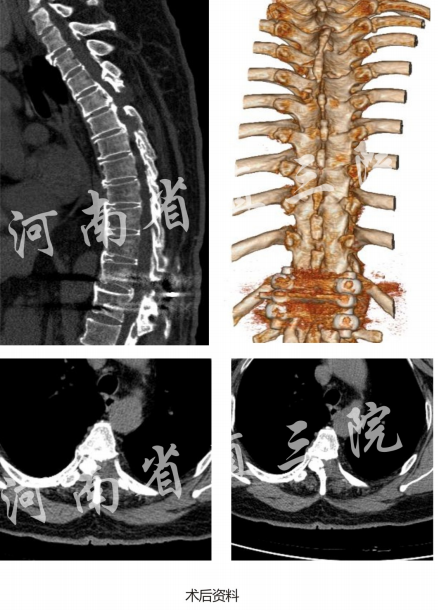

全可视脊柱内镜治疗胸椎间盘突出(腹侧钙化)

患者:张X女67岁

入院诊断:1)T4-5/T5-6胸椎间盘突出(腹侧钙化)